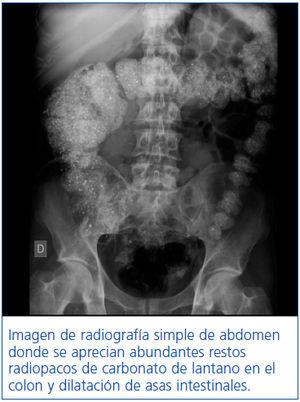

Transcurrido un mes de la última alta hospitalaria, acude de nuevo con dolor abdominal, estreñimiento, náuseas y vómitos, ingresando esta vez en nuestro Servicio de Nefrología. A la exploración presenta peristaltismo conservado y dolor abdominal difuso, la analítica es anodina (ausencia de leucocitosis, amilasa y lipasa dentro de rangos normales). En las radiografías simples de abdomen previas y actuales, como se muestra en la figura 1, se observan abundantes restos de carbonato de lantano en el colon y dilatación de asas intestinales coincidiendo con la toma de carbonato de lantano, 3 g/día desde hace tres meses. Se diagnostica pseudoobstrucción intestinal secundaria a estreñimiento pertinaz por carbonato de lantano; se suspendió dicho fármaco, se realizaron dos enemas de limpieza y se asoció laxante osmótico por vía oral (Duphalac®), con resolución completa del cuadro clínico.

Figura 1. Pseudoobstrucción intestinal por carbonato de lantano